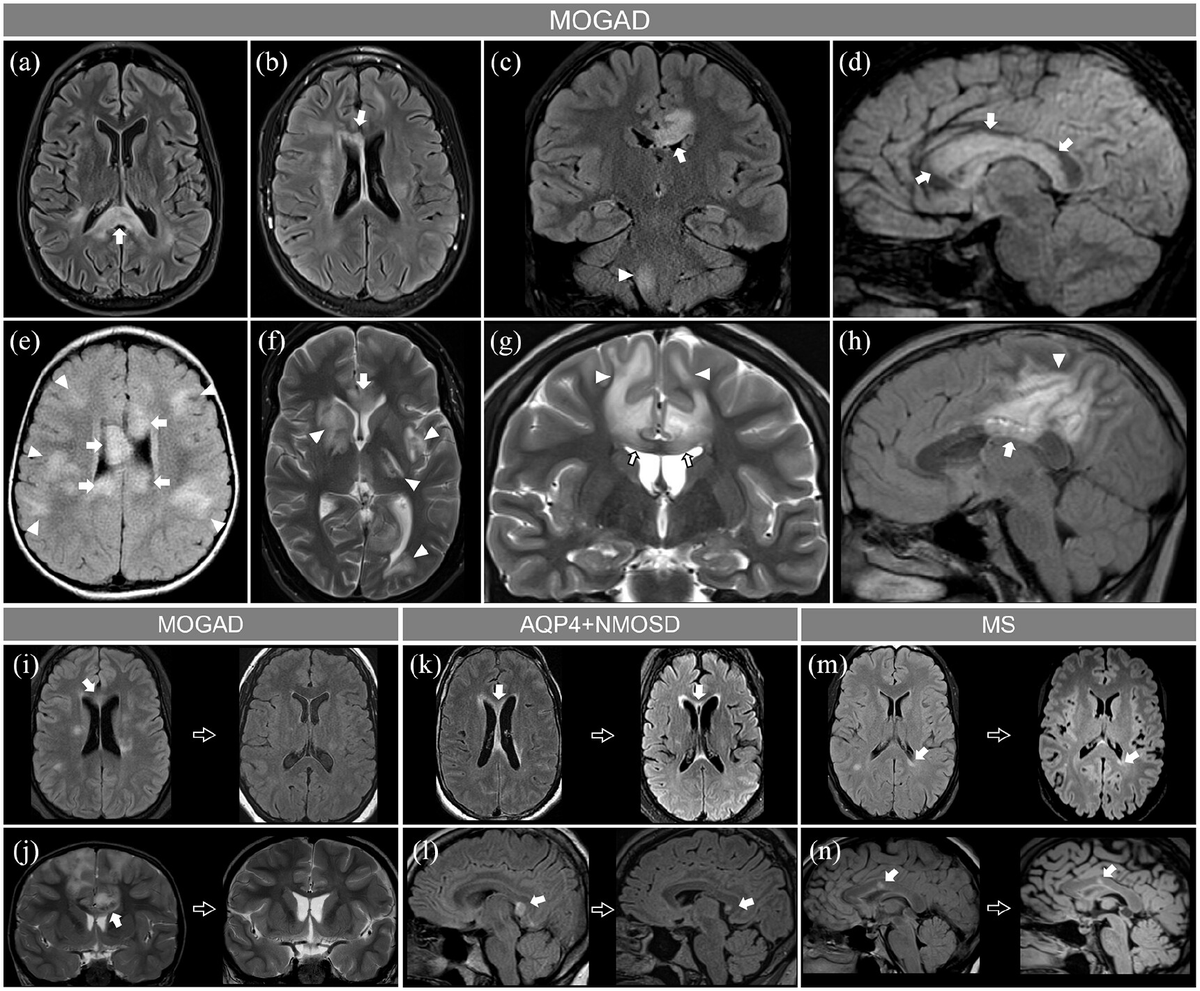

From www.frontiersin.org

Frontiers MRI Prognostic Factors in Multiple Sclerosis, Neuromyelitis How Long Do Ms Lesions Last How long do ms lesions stay active? People with ms generally experience a progression of ms symptoms and severity throughout their lives. A lesion can stay active and may cause symptoms for several days to weeks after the initial appearance of the lesion. If the lesion does not light up, then it is likely to be an older lesion, and. How Long Do Ms Lesions Last.